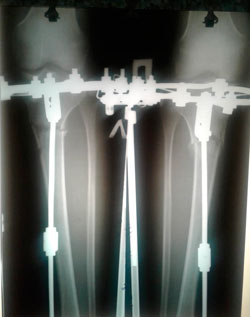

Дата операции - 19.06.2018г.

Дата снятия аппаратов - 15.10.2018г.

Срок лечения - 115 дней.